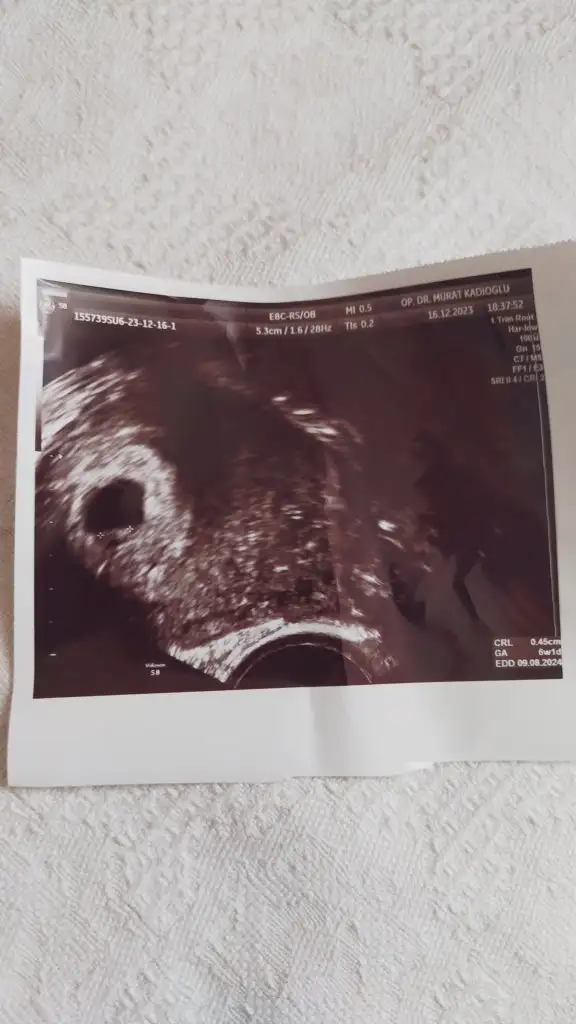

U umaycayBuraya kendi ultrason çıktımı bırakıyorum . Çıktıdan, nispeten iyi bir cihaz olduğu anlaşılıyor . Bazı çıktılar çok bulanık , ordan da cihazın eski ya da bozuk olduğu anlaşılıyor. Sen bence farklı bir doktora git . Çünkü 10 gün beklemek için çok uzun . Burda kese görünmedi , bebek görünmedi diyen yorumlar çok fazla . Çoğu da başka doktora gidip bebekleri gördüler canım . Sende git ki için rahatlasın Eki Görüntüle 3353389

Buraya kendi ultrason çıktımı bırakıyorum . Çıktıdan, nispeten iyi bir cihaz olduğu anlaşılıyor . Bazı çıktılar çok bulanık , ordan da cihazın eski ya da bozuk olduğu anlaşılıyor. Sen bence farklı bir doktora git . Çünkü 10 gün beklemek için çok uzun . Burda kese görünmedi , bebek görünmedi diyen yorumlar çok fazla . Çoğu da başka doktora gidip bebekleri gördüler canım . Sende git ki için rahatlasın

Canım cidden senin ultrasonda görüntü kalitesi çok net ben özele gitmeme rağmen bu kadar net çıkmadı açıkçası bu biraz moral bozucu pazartesi günü gideceğim inş kesenin içinde bebeği görürüz ve kalp atışını duyarızBuraya kendi ultrason çıktımı bırakıyorum . Çıktıdan, nispeten iyi bir cihaz olduğu anlaşılıyor . Bazı çıktılar çok bulanık , ordan da cihazın eski ya da bozuk olduğu anlaşılıyor. Sen bence farklı bir doktora git . Çünkü 10 gün beklemek için çok uzun . Burda kese görünmedi , bebek görünmedi diyen yorumlar çok fazla . Çoğu da başka doktora gidip bebekleri gördüler canım . Sende git ki için rahatlasın Eki Görüntüle 3353389